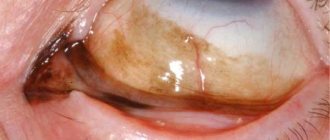

Причины Причины развития рака глаз на сегодняшний день не выяснены, но существует ряд факторов,